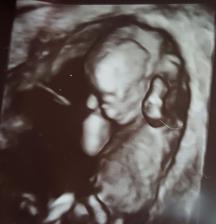

Gratuluji, je to veliký zázrak!!🙂 Z ničeho je malý tvoříček!! 🙂 už se těšíme na druhé,l ale ješte si poškáme, termín máme 01.01.2017